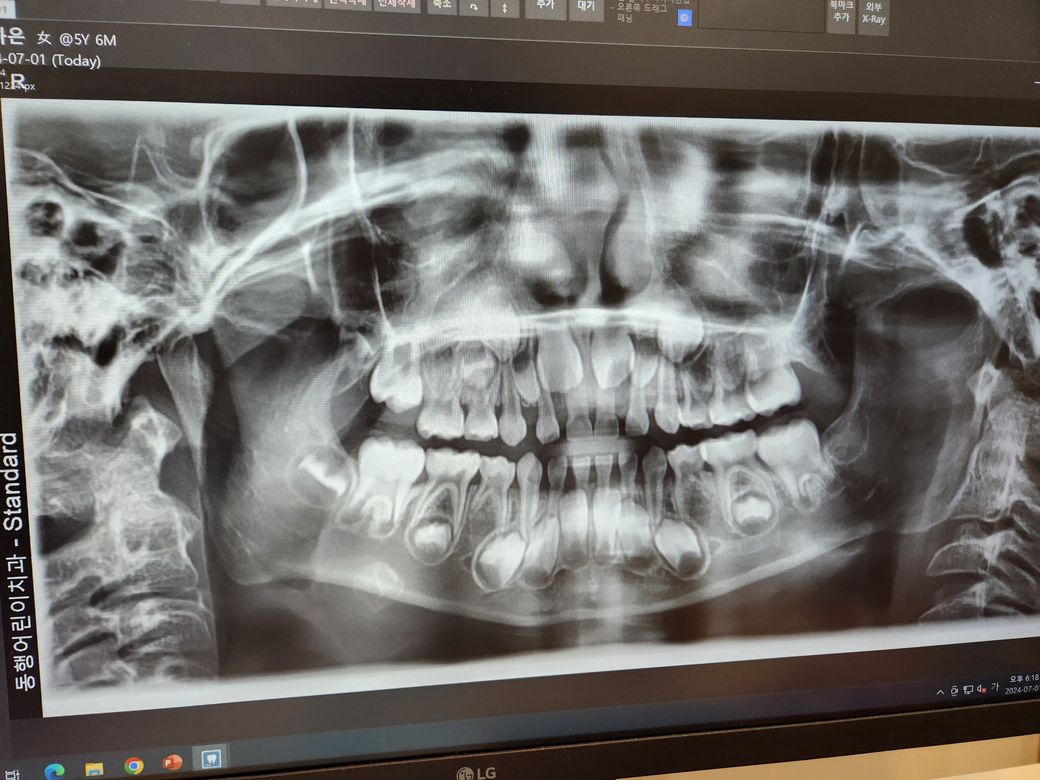

제가 태어날 때 부터 유치가 빠지질 않았습니다. 성인치아가 올라오질 않아서요....기형아라고 했던 거 같은데...

저희 딸이 12월생 7세 입니다.

걱정이 되서 치과진료를 봤는데... 치과 의사분께서 기형아라고 합니다 ㅜㅜ.... 성인치아 뿌리가 없는 게 6개가 넘는 다고 하네요...

엑스레이 상의로 보면 아래 쪽 작은 어금니가 보이지 않는거 같습니다. 최대한 유치를 오래 사용하셔서 나중에 문제가 생기면 임플란트를 하셔야됩니다.

엑스레이 사진을 봤을 때 기존치아 밑에 동그란 형태의 영구치가 안보이는 것들은 모두 유치만 자라는 치아입니다.

현재 양쪽 아래 네번째 치아 (첫번째 작은어금니, 제1소구치 부위, 유구치 상태), 오른쪽 양쪽 다섯번째 치아 (제2소구치 부위)가 결손으로 의심됩니다. 위 사진상에서는 좌우가 반전입니다.